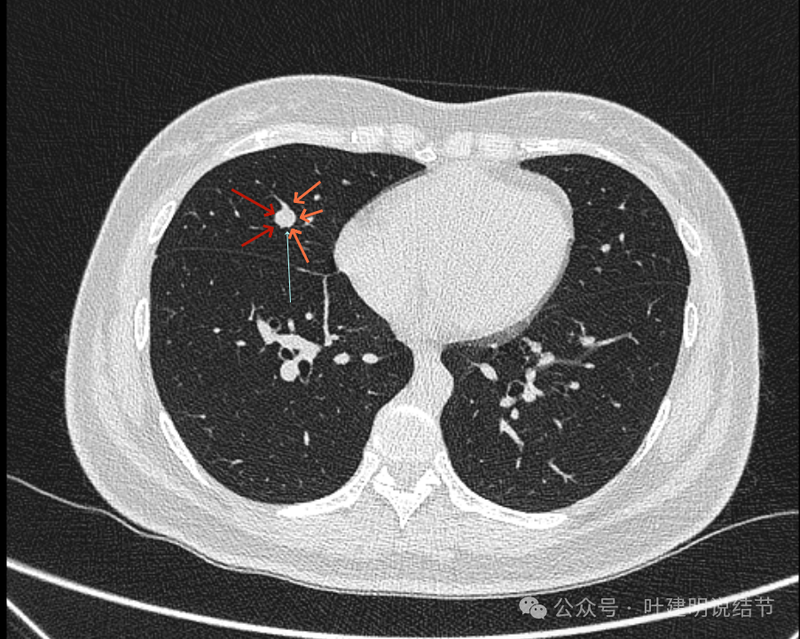

病灶出现,图上标注的桔色箭头所指的是肺血管;红色箭头所指的是病灶;天蓝色细线指的是血管与结节之间的间隙。病灶实性,与血管挨得近,但没有紧贴或侵犯。

病灶与血管间仍有低密度线状,血管在此处刚好分叉似的。

病灶有膨胀性,血管贴得近。

似乎见血管围着结节灶,两者紧贴,密度略有不同,导致上图中血管受压成细条状,病灶是软组织密度。

看着像靠心脏这一侧的半圈是血管受压形成的包膜似的,但靠胸肋侧没有血管,所以略偏白些的血管影在外侧见不见,外侧见到的是病灶的边缘,比较光滑,两者之间密度不同(天蓝色细线所指是两者分界,虽紧挨却密度不同)。

上图也示病灶与血管的关系。

上图像病灶位于中央,周围有三支不同血管围着它。

确实是三支血管围着病灶,中间的是结节,另三处均是血管。